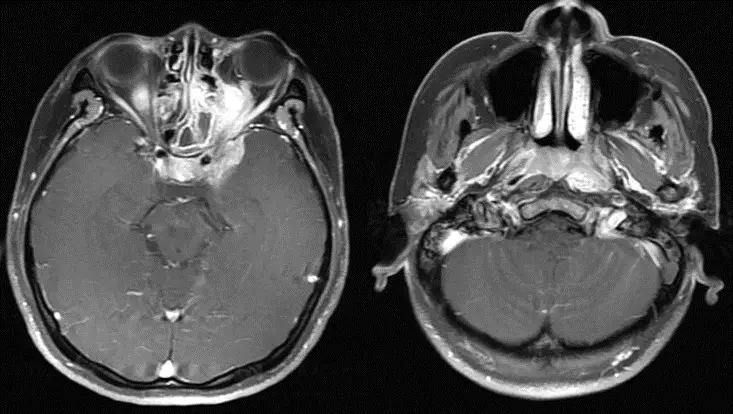

37歲女性病人,因左上眼瞼下垂與複視而求診,靜脈注射顯影劑磁振造影(如圖),下列何者為最可能之診斷?

從第一張對比劑增強T1加權軸向影像可見:

• 左側海綿竇區域明顯不對稱增大

• 內部呈不均勻實質性強化,包繞左內頸動脈,無典型“flow void”信號

從第二張較低層次影像:

• 左側鼻咽頂及咽後壁同側出現同質性增強病灶

• 病灶沿顱底向上延伸,可見骨質微破壞及傍顳肌群失神經萎縮現象

整體符合一個由鼻咽區起始,經顱底直接侵襲及鞘狀(perineural)擴散至海綿竇的腫瘤過程。